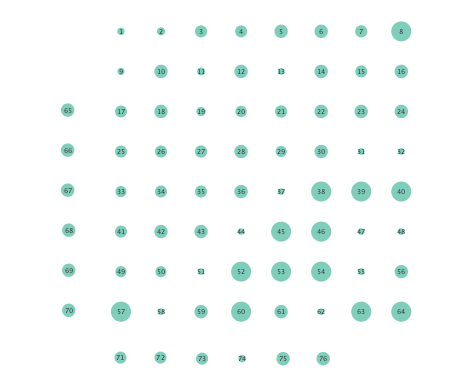

In order to assess the information-routing abilities of brain regions before and after seizure onset, comparisons of the so-termed betweenness centrality were done. Betweenness centrality of a node computes the fraction of shortest paths between all node pairs that traverse the given node, and it is useful to identify the key information transmitting hubs in a network; see e.g., [24] for more details. The per-node betweenness centrality for each inferred network are depicted in Figure 4, with node radii similarly encoding the computed values. Little variation between preictal and ictal betweenness centralities is seen for the linear model (Figures 4 (a) and (b)), while variations are slightly more marked for the K-SVARM, see Figures 4 (c) and (d). It can be seen that modeling nonlinearities reveals subtle changes in information-routing capabilities of nodes between preictal and ictal phases.

Moreover, the performance of K-SVARM with data-driven kernel selection was also tested. Figure 7 illustrates the per node degree as well as the closeness centrality of networks inferred from preictal and ictal phases. Consistent with Figures 3 and 6, Figure 7 again reveals universal decrease in node degrees as well as closeness centrality at seizure onset.